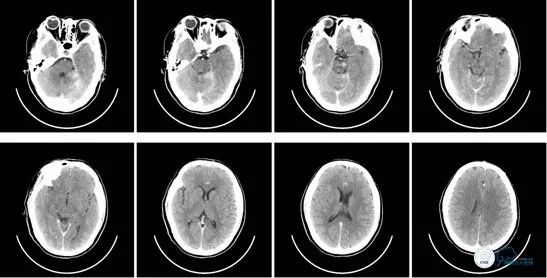

入院时急查头颅CT示:颅脑未见明显异常。ASPECT评分10分。

入院时急诊头颅CT:

图1

术后即刻头颅CT:可见少量造影剂渗出,排除术后出血。

术后8小时头颅CT:

图13